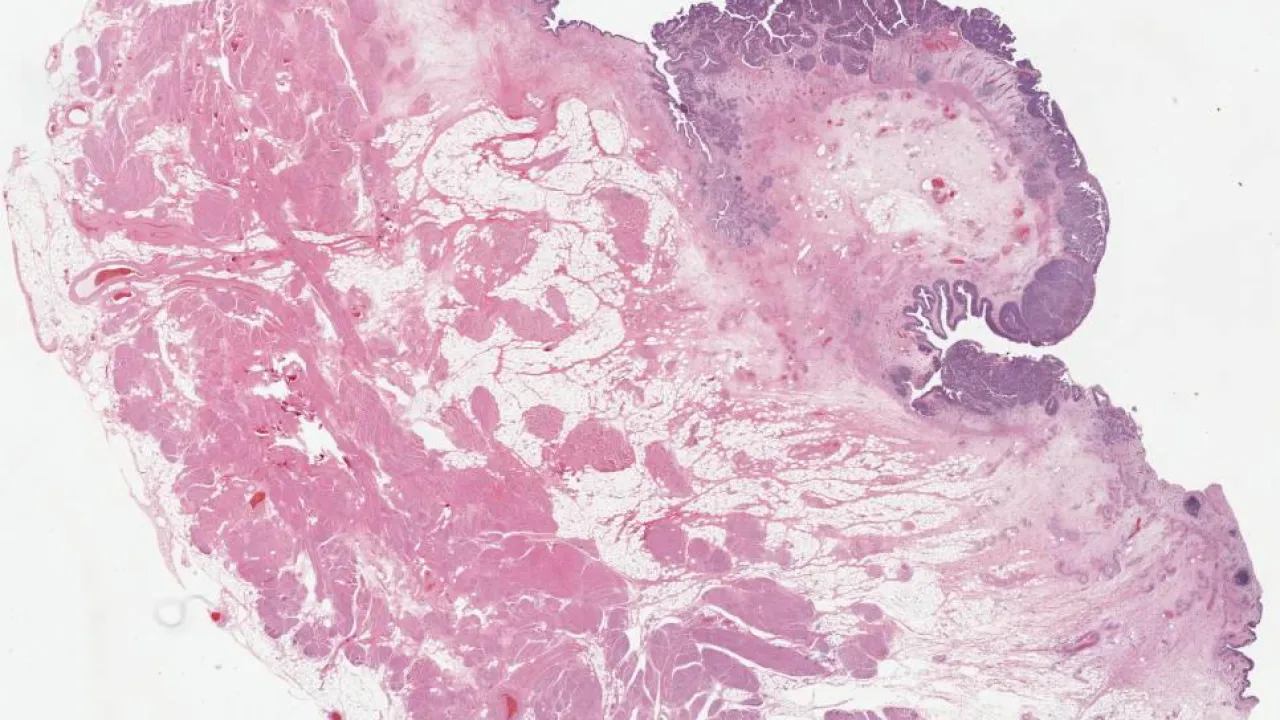

Pancreas, Intraductal papillary mucinous neoplasm